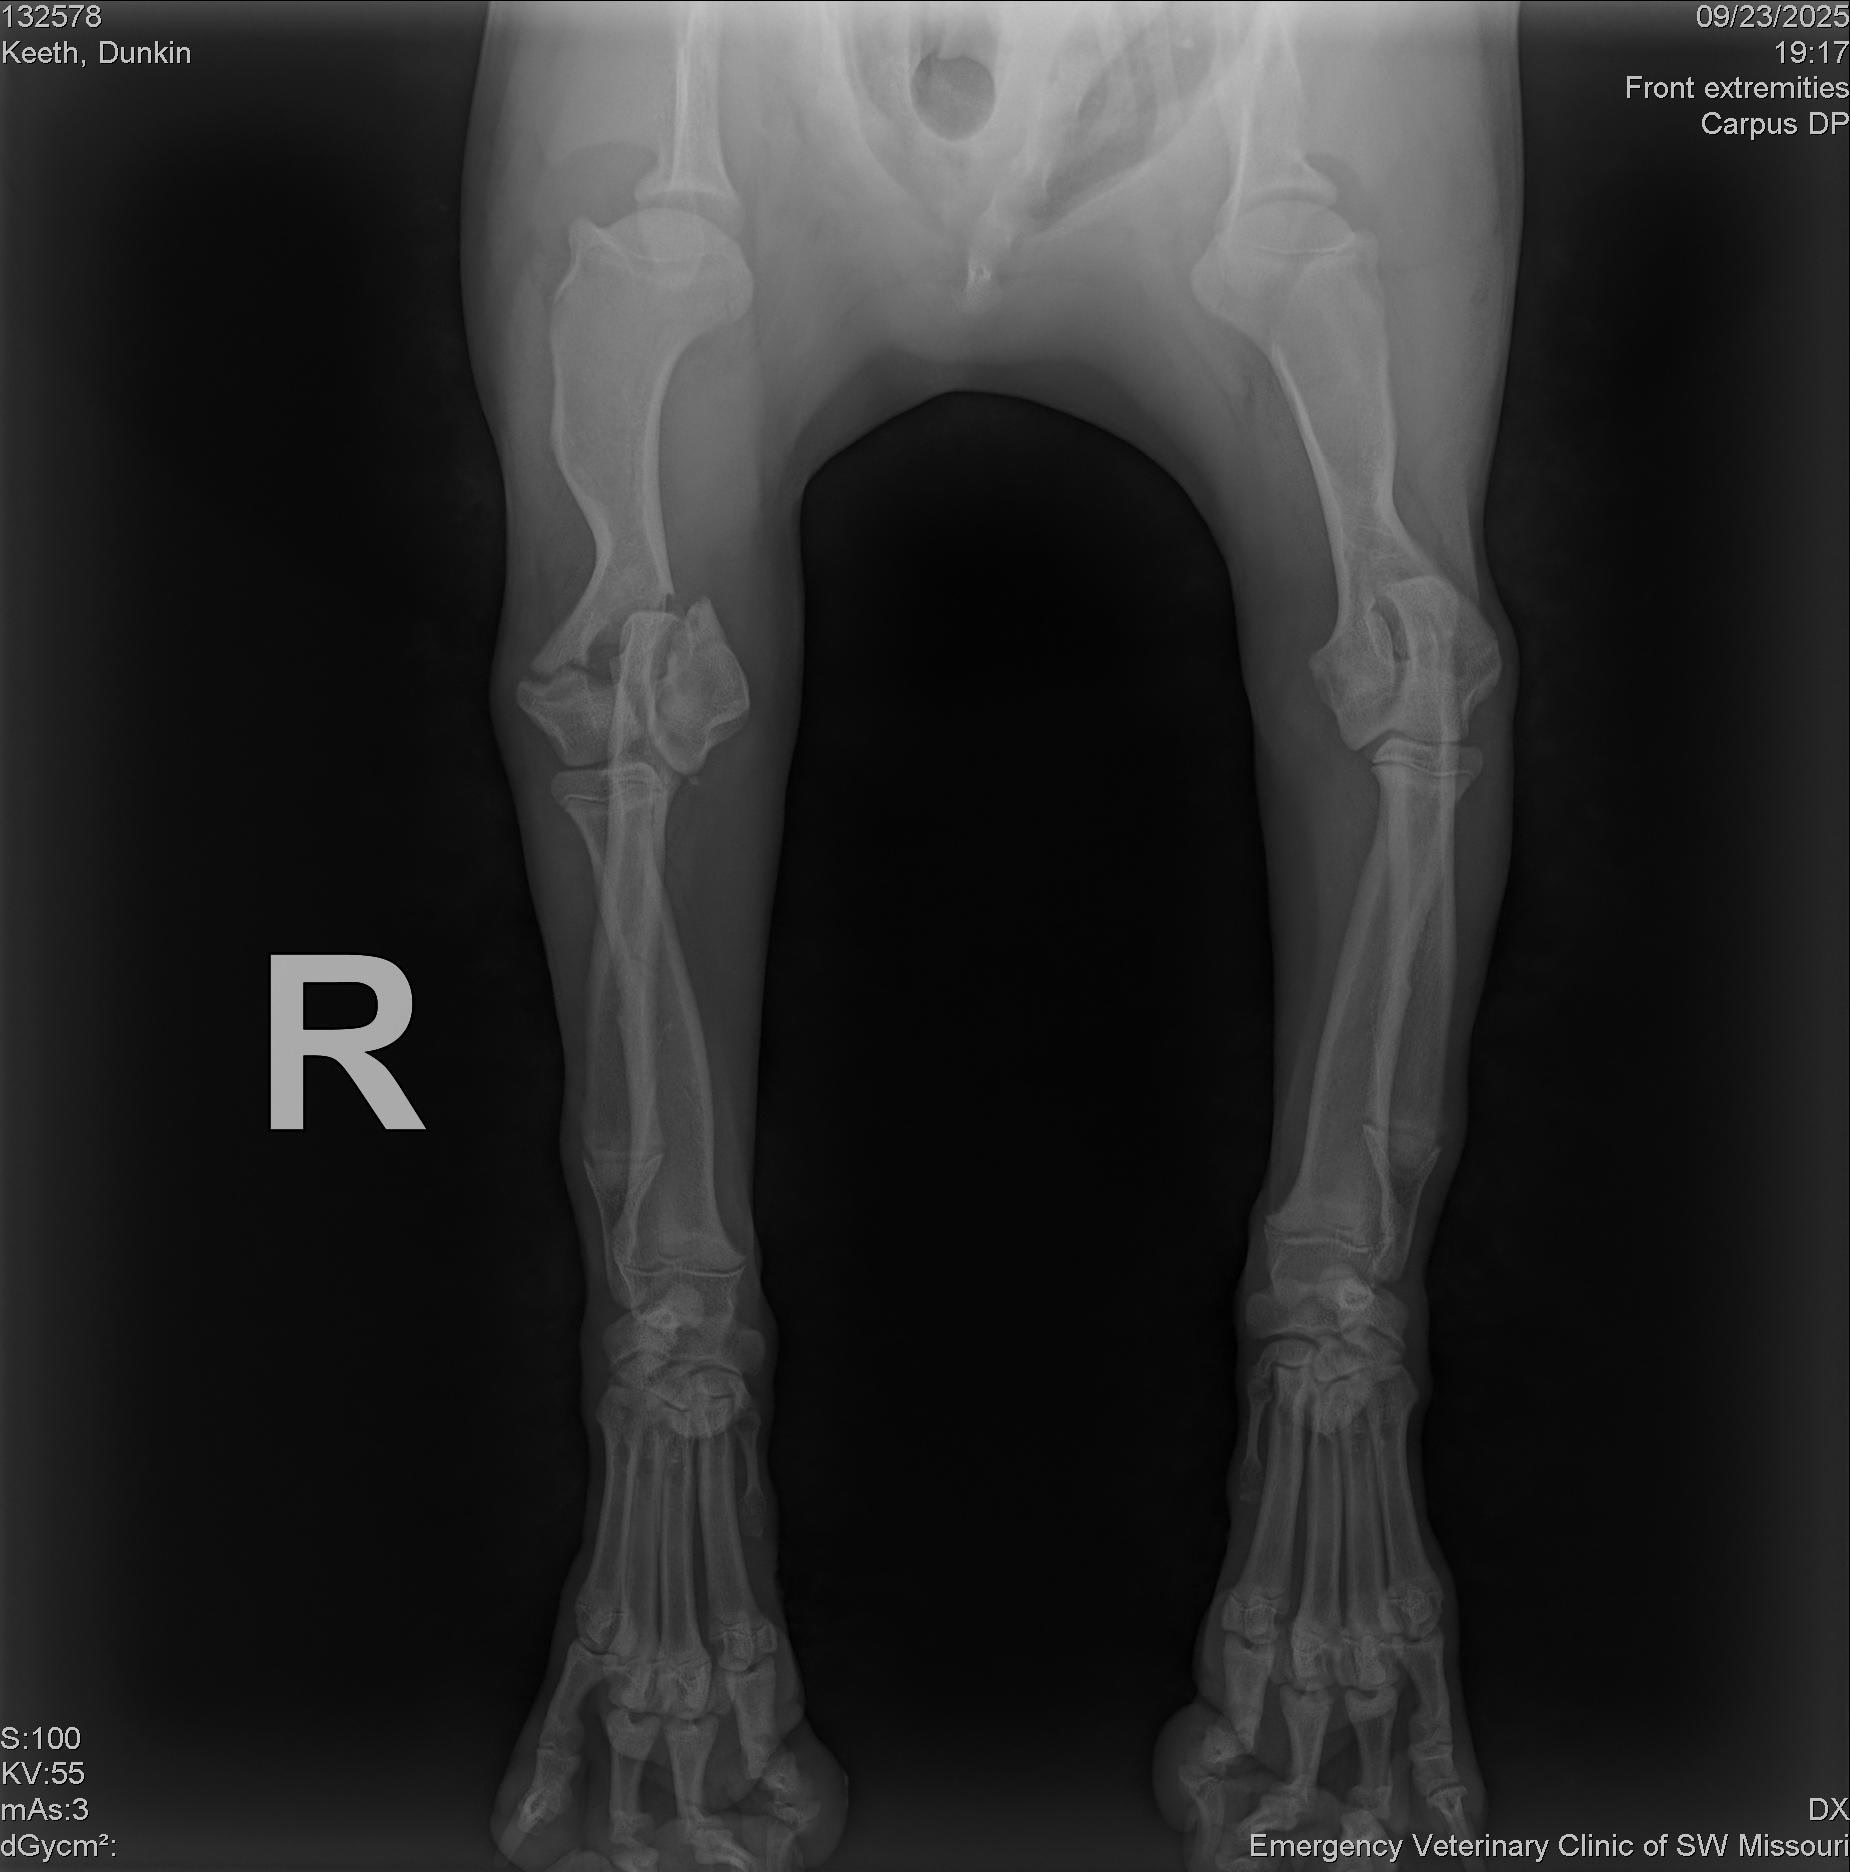

A few days ago, Dunkin hurt his leg, and the vet gave us heartbreaking news: he has fractures in both the lateral and medial condyles of his leg. To fix it, he needs surgery that costs $6,000. If we can’t raise the money, the only other option is amputation for about $1,000.